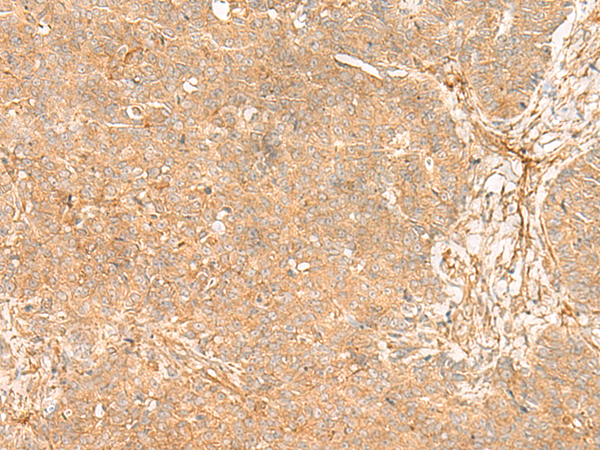

IHC (Immunohiostchemistry)

(Immunohistochemistry of paraffin-embedded Human ovarian cancer tissue using FLNC Polyclonal Antibody at dilution of 1:35(×200))